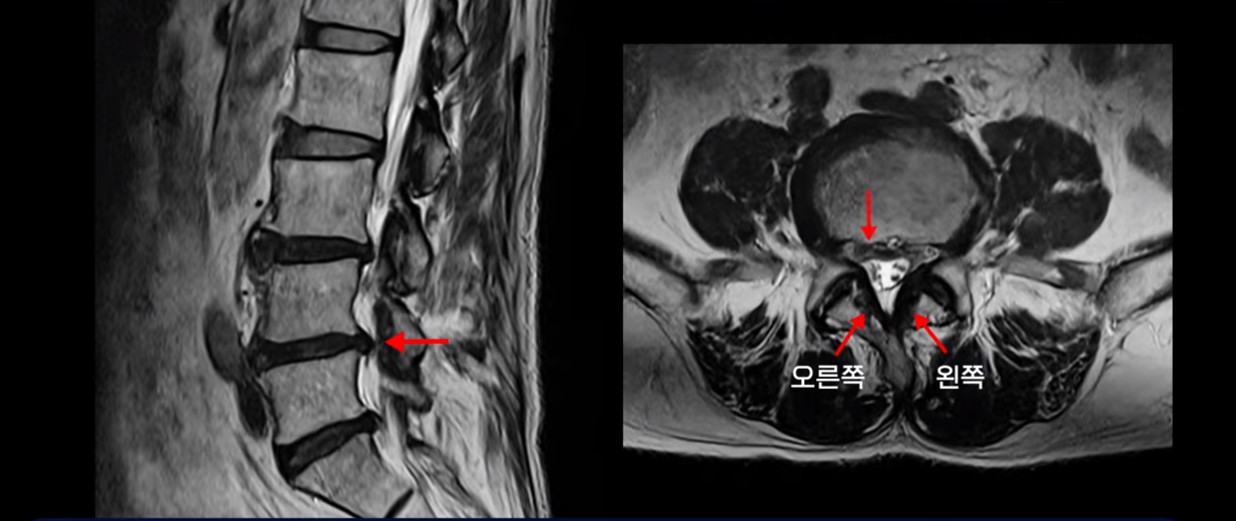

이분 MRI를 보면서 간단히 설명 드린 후 어떻게 허리에서 신경이 눌려서 발목이 마비된 환자가 수술 없이 치료가 될 수 있는 건지, 또 치료는 구체적으로 어떻게 하는 건지 자세히 설명 드리겠습니다.

이분은 허리디스크 탈출도 있고 중심성 협착도 있습니다.

4번 5번 중심성 협착을 보면 왼쪽 황색인대가 오른쪽에 비해 많이 두꺼워져 있습니다.

이 밀려나온 디스크는 최근 발생한 게 아니고 오래 전 발생하여 이미 굳어버린 디스크 수핵으로 보입니다. 보시다시피 앞에서는 밀려나온 디스크 뒤쪽에서는 두꺼워진 황색 인대가 신경을 눌러 발목마비가 온 걸로 보입니다.